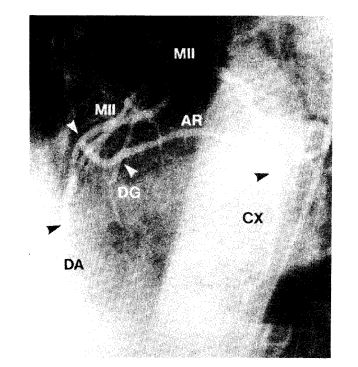

Entre mayo de 1995 y mayo de 1998 se operaron 1.023 pacientes consecutivos utilizando conductor arteriales, una o dos arterial mamarias y arteria radial. La mamaria izquierda se empleó in situ y la mamaria derecha como injerto libre o in situ, ambas en combinación con la arteria radial. Esta última se conectó a la mamaria izquierda a través de una anastomosis en T o en Y o, en menor proporción, emergiendo de la porción ascendente de la aorta.

Se realizó un promedio de 3,3 puentes/paciente. La arteria mamaria izquierda se utilizó en el 100% de los casos. La mamaria derecha se empleó en el 21,7% y la radial en el 100% de los pacientes. La mortalidad hospitalaria fue del 2,5% (26 pacientes) y 32 (3,1%) sufrieron un infarto perioperatorio. Los primeros 62 pacientes fueron estudiados angiográficamente antes del alta y se obtuvo un 98,4% de permeabilidad en los conductor empleados. La media de seguimiento fue de 25,0 ± 9,6 meses (rango 1-48 meses).